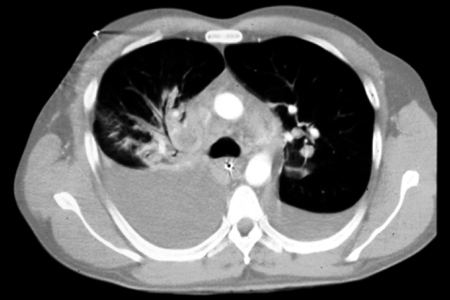

Anthrax

Chest CT reveals perihilar lymphadenopathy, perihilar infiltrates, and a widened mediastinum

Borio et al. JAMA. 2001;286:2554-2559